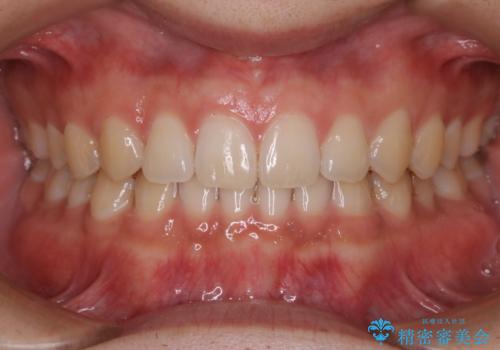

- 上のすきっ歯が気になるとご相談にいらした方です。上下顎ともにスペースがあったため、インビザラインFULLにて見た目と噛み合わせの改善も同時に行いました。

元々は上前歯のみの部分矯正をご希望されていましたが、下の歯もスペースがあり、噛み合わせ的にも上のみの部分治療は難しいことをお話ししました。前歯のみの部分矯正を行った場合、前歯の隙間だけが閉じて奥歯が噛めなくなってしまう場合もあります。インビザラインFULLにて治療することで、噛み合わせと見た目を同時に改善させることができ、大変喜んでいただけました。